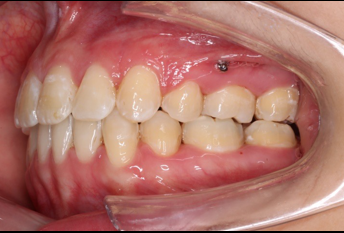

2019.08.06  术后  10个月复查

宏观评价:面部对称,面下三分一比例协调,上下唇凸度正常,上颌牙列内收转矩控制良好,下颌后缩改善,颏唇沟变得更加柔和,术后达到基本直面型。

迷你观评价:上下牙齿中线与面中线对齐,笑弧协调,微笑时牙龈暴露量正常,微笑时横向正常,左右唇基本对称。

微观评价:牙齿整齐,咬合关系良好,上下前牙转矩及突度控制良好,磨牙关系I类,尖窝咬合关系良好,OB,OJ正常。